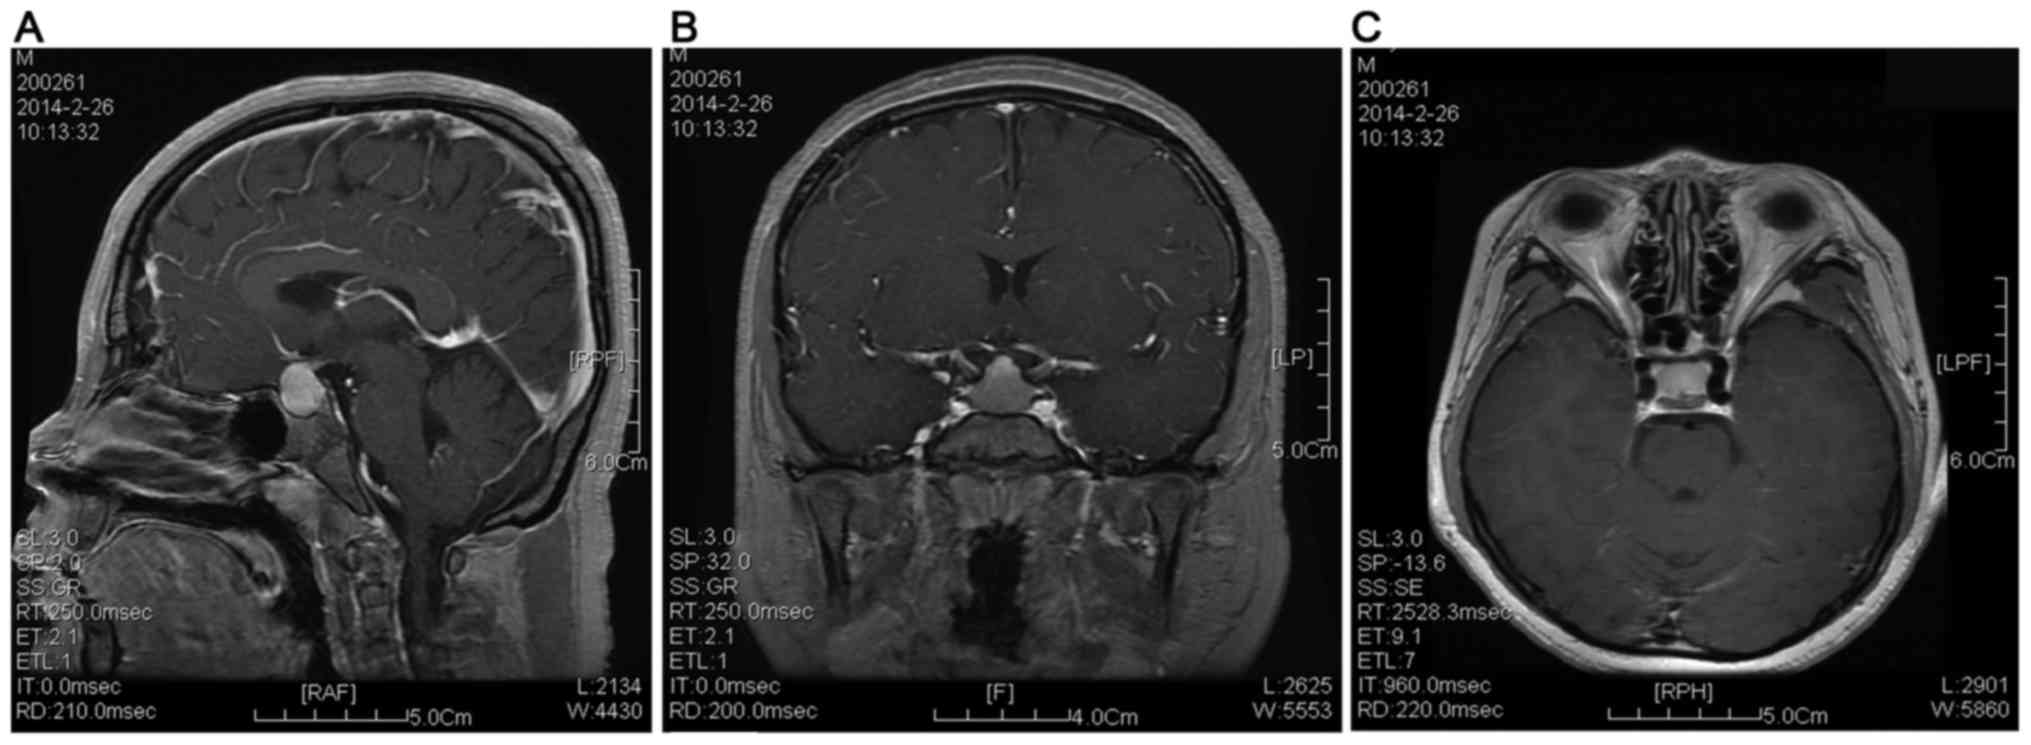

A 14-year-old male patient of non-consanguineous parents was referred to the Department of Pediatrics of the General Hospital of Tianjin Medical University (Tianjin, China) due to obesity, short stature and muscle weakness in February, 2014. He had shown progressive weight gain, delay in growth, constipation, muscle weakness and poor academic scores over the past 3–4 years. Physical examination results were as follows: Body temperature, 36.5°C; heart rate, 60 beats per min; respiratory rate, 20/min; blood pressure, 100/70 mmHg; body weight, 59 kg (>97th percentile); height, 139 cm (<3rd percentile); and body mass index, 30.5 (>97th percentile). The thyroid gland was enlarged. Abdominal examination indicated hepatomegaly and cardiac examination indicated a slightly distant heart sound without murmurs. The bilateral testicular volume was 25 ml as measured by a Prader orchidometer (Creative Health Products, Ann Arbor, MI, USA) and stretched penile length was 5 cm. No pubic or axillary hair was observed. Laboratory results are summarized in Table I. Laboratory parameters associated with renal function were normal. Thyromegaly accompanied with low-intensity echoes were identified by thyroid ultrasound. Abdominal ultrasound revealed hepatomegaly. Delayed bone age was confirmed according to X-ray imaging of the left wrist and hand (Fig. 1) with an estimated bone age of 10 years. Cranial magnetic resonance imaging (MRI) indicated enlargement of the pituitary gland (Fig. 2), and pituitary hyperplasia was suspected. Based on these results, the patient was finally diagnosed as VWGS. As a treatment, replacement therapy was given using levothyroxine with an initial dose of 25 µg/m2/day, which was gradually increased to 100 µg/m2/day. The patient was followed up for 6 months and the levels of free triiodothyronine (T3), T4 and TSH were 4.35 pmol/l, 18.65 pmol/l and 3.31 µIU/ml, respectively. The body height showed an increase of 5 cm after the treatment.

Figure 2.

Pituitary magnetic resonance image indicating enlargement of the pituitary gland, and pituitary hyperplasia was suspected based on the (A) sagittal, (B) coronal; and (C) transverse views.

Weight gain has been regarded as a symptom of hypothyroidism. In the complete absence of thyroid hormone, basal metabolic rate or resting energy expenditure was reduced by 30% or even 59% (28). In the present case, the patient showed elevation of cholesterol liver enzymes and hepatomegaly, which may be associated with hypercholesterolemia induced by hypothyroidism. Besides, hypothyroidism has been reported to have an important role in the pathogenesis of nonalcoholic fatty liver disease (NAFLD) (29). Specifically, Chung et al (30) reported that NAFLD was more severe and liver enzyme was significantly elevated in patients with hypothyroidism compared to those in normal subjects. In the present case, pituitary enlargement was revealed by cranial MRI, which may result in long-term hypothyroidism. In addition, the thyrotroph hyperplasia may lead to sella turcica expansion and pituitary hyperplasia.